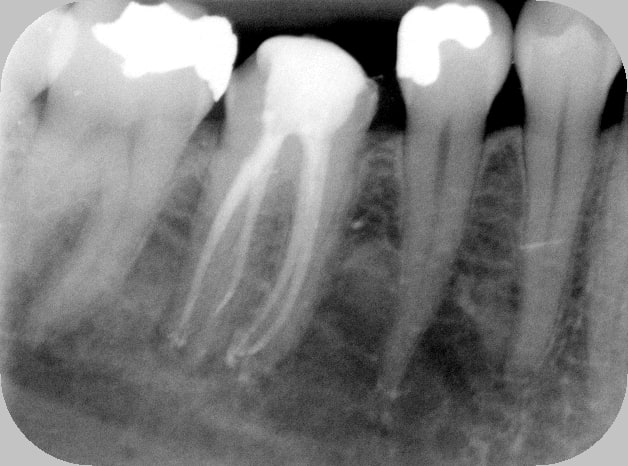

Putain de sa mère, j'ai pété un R25 à l'apex du 5°canal... Canal lingual en C, j'en étais au 8° canal pour l'instrument, j'aurai pas dû être joueur.

1h en comptant la dépose de la couronne, la RCR et la pro en bloc technique.